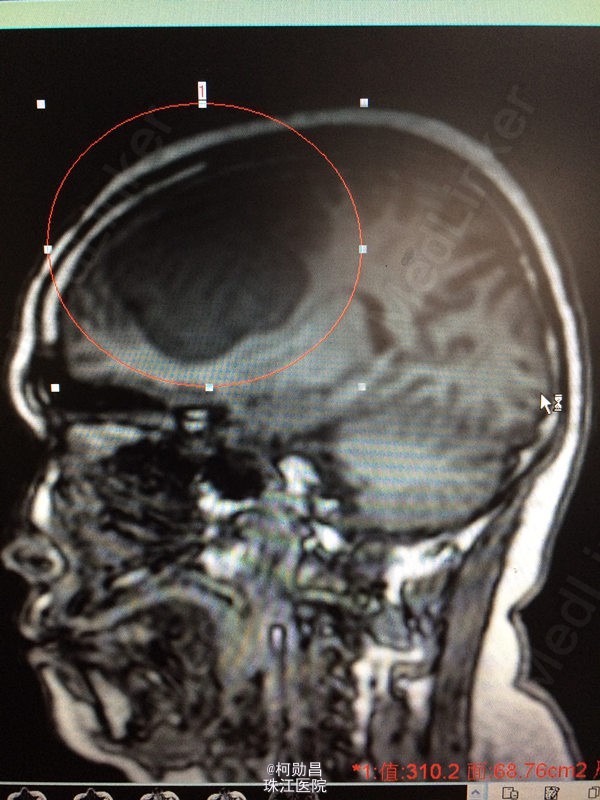

患者 62岁女性,因“发现右侧大脑镰旁肿物2天”入院,症状表现为:反应迟钝,懒言,无其他症状。MR提示“右侧大脑镰旁肿瘤,考虑脑膜瘤”